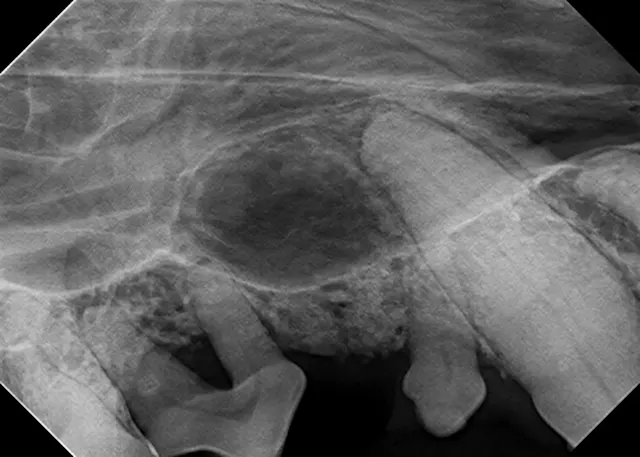

The relatively simple parallel technique is used to image the mandibular caudal cheek teeth on small dogs and cats.

For large dogs, use this technique to image teeth from the third premolar to the last molar. This portion of the oral cavity has room enough to place the sensor parallel and adjacent to the desired teeth, on the lingual aspect of the mandible. Then, aim the tube head perpendicular to the sensor.

This technique, which is used to image the rostral mandible and entire maxilla, is the only technique that produces an image without distortion when done correctly. Some technicians find the bisecting angle technique difficult to grasp; however, it can be simplified with proper patient and equipment positioning.

For example, image the caudal cheek teeth in the maxilla with the tube head at a 60° angle from the horizon.2 When the patient is positioned with the maxilla parallel to the horizon, the sensor can also be placed parallel to the horizon (ie, inside the oral cavity and adjacent to the desired teeth), making it much easier to visualize the angle.

Place the sensor horizontally inside the oral cavity, with the cusp tip of the desired teeth at the edge of the sensor. Placing the sensor inside the oral cavity will provide enough room to catch the radiograph image.

Radiographs should be taken in the same order each time. Starting with the right maxillary molars, move the sensor and tube head around the entire arch until the left caudal maxilla is reached. Then, position the patient in ventral recumbency and repeat the process, starting with the left mandibular molars. Continue around the arch until the right caudal mandible is reached. This sequence is suggested because full-mouth-series templates included in most digital software programs are arranged in this order and will result in the mirror image for correct viewing of radiographs.